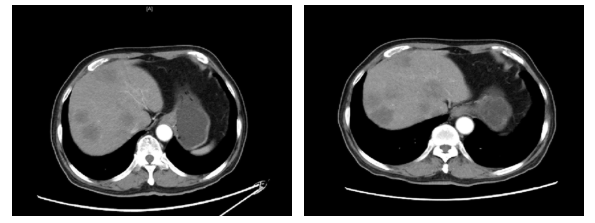

2019.11.18 腹部CT:肝脏多发结节(图2),考虑转移。

图2. 腹部CT(2019.11.18)